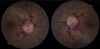

What does this fundoscopy show?

CRVO (haemorrhages, dilated veins and disc swelling)